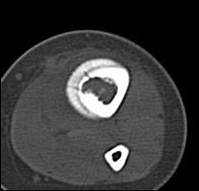

左胫骨中下段见一不规则虫蚀样骨破坏,走形方向与胫骨长轴一致,边缘轻度硬化,伴明显骨膜增生,ct见破坏区内见磨玻璃样密度,其旁软组织钟胀,内见不规则钙化。

左胫骨中下段见一不规则虫蚀样骨破坏,走形方向与胫骨长轴一致,边缘轻度硬化,伴明显规则的骨膜增生,ct见破坏区内见磨玻璃样密度,其旁软组织钟胀,内见不规则钙化。

病史资料不完善,根据年龄、部位、及影像学表现,主要表现胫骨骨干囊性骨质破坏,骨皮质受累,局部骨膜反应,未见骨膜破坏及瘤骨,未见放射状骨针。 首先要考虑胫骨转移瘤,建议进一步检查,除外视网膜母细胞瘤,神经母细胞瘤,肾母细胞瘤,肾上腺等恶性肿瘤骨转移。排除转移瘤后考虑嗜酸性肉芽肿可能性大,患者年龄5岁,尤文氏瘤不太考虑,骨肉瘤也不太符合,骨髓炎待排,影像表现不太支持。建议进一步检查,除外原发恶性肿瘤胫骨转移后,考虑嗜酸性肉芽肿。必要时穿刺活检。